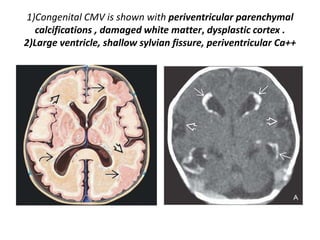

1)Congenital CMV is shown with periventricular parenchymal

calcifications , damaged white matter, dysplastic cortex .

2)Large ventricle, shallow sylvian fissure, periventricular Ca++